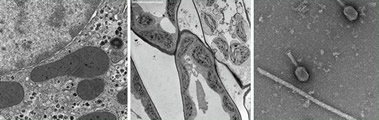

EMS公司自豪地推出一款無(wú)鈾染液,對(duì)TEM以及所有的染色應(yīng)用而言,它是一種全新的比對(duì)染色試劑,可以取得和醋酸雙氧鈾一樣的實(shí)驗(yàn)結(jié)果。

染色速度快(一分鐘),無(wú)輻射擔(dān)憂。有時(shí)候,為了增強(qiáng)比對(duì)效果,可以使用檸檬酸鉛負(fù)染。為了防止沉淀發(fā)生,使用室溫蒸餾水溶解染液。

Uranyless無(wú)鈾染液的PH值大約在6.8-7之間。壓力瓶(有噴嘴)保存,延長(zhǎng)了保質(zhì)期,減少了二氧化碳的污染。

無(wú)鈾染液可以應(yīng)用在很多生物組織上,例如:腸、骨骼、心肌、肝臟、腎臟、神經(jīng)、細(xì)胞培養(yǎng)、植物組織等,還有抗菌素、細(xì)菌和高分子材料。無(wú)鈾染液的穩(wěn)定性和可重復(fù)性都表現(xiàn)的非常理想,圖片如下